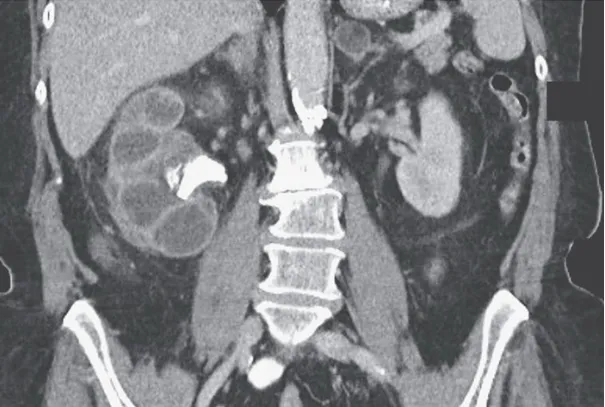

Hematuria e perda rápida da função renal em pacientes com câncer devem levantar suspeita de trombose da veia renal, mesmo sem contraste. Imagens não contrastadas e Doppler podem ser ferramentas-chave nesse contexto.